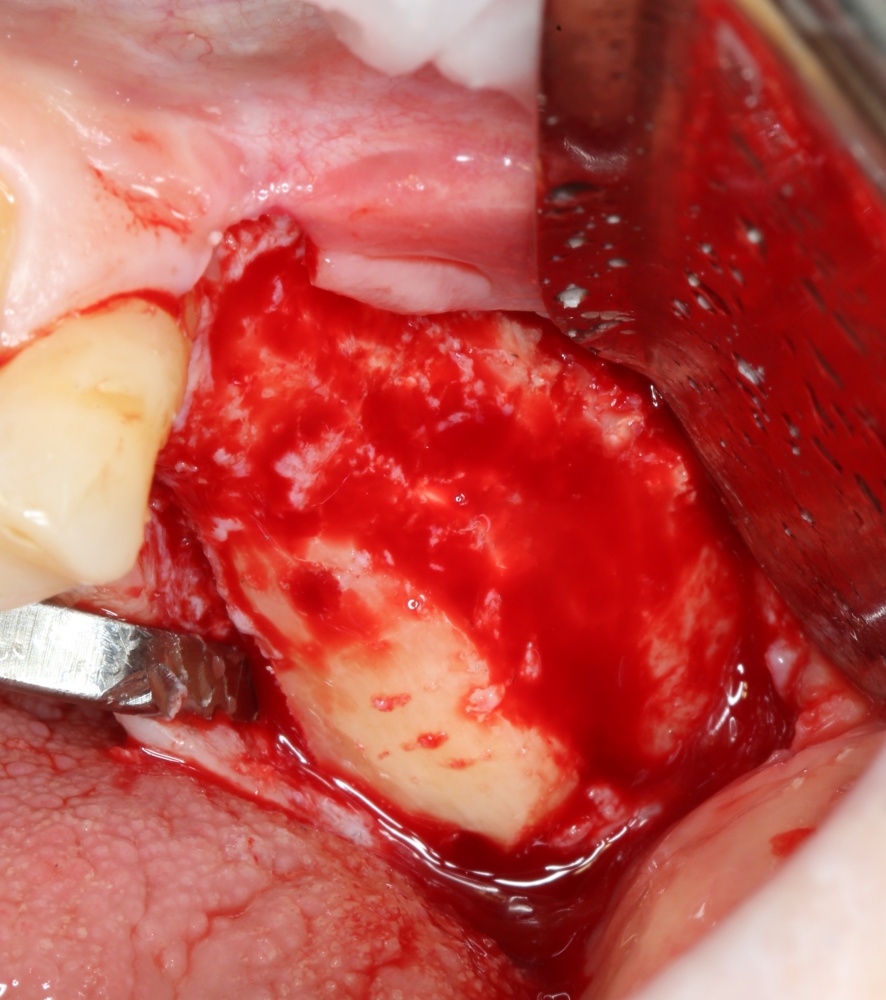

Как на фотографии выше — из-за целого ряда вмешательств и существовавшего ранее ороантрального соустья можно сказать, что от слизистой оболочки верхнечелюстной пазухи почти ничего не осталось. Можем ли мы как-то закончить эту работу? Легко:

Первая операция — мы не можем сразу поставить имплантат из-за почти полного отсутствия кости между полостью рта и дном верхнечелюстной пазухи: